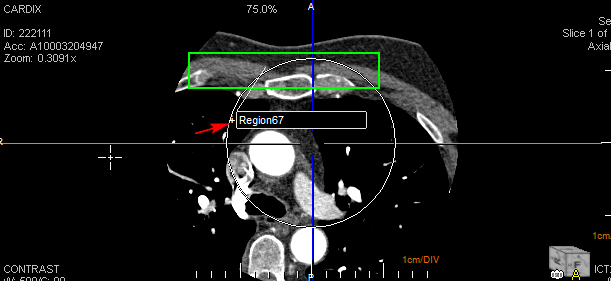

Start by highlighting an area of the image using a ROI tool. In this case, the Rect ROI is used.

After the image is highlighted, right-click to display the Annotations menu. This consists of Deselect, Show Annotations, ROI Histograms, Filled, Delete, and Layers. Any number of layers can be added. You can also choose to apply a Annotation Layer to an entire Frameset by selecting the option Apply to entire frameset. Note that this option may not be applicable for Key Objects as Key Objects may contain different framesets.

Click the Show Annotations option. The annotations for the highlighted area of the image are displayed. To undo these changes, right-click again, and click the Show Annotations option.